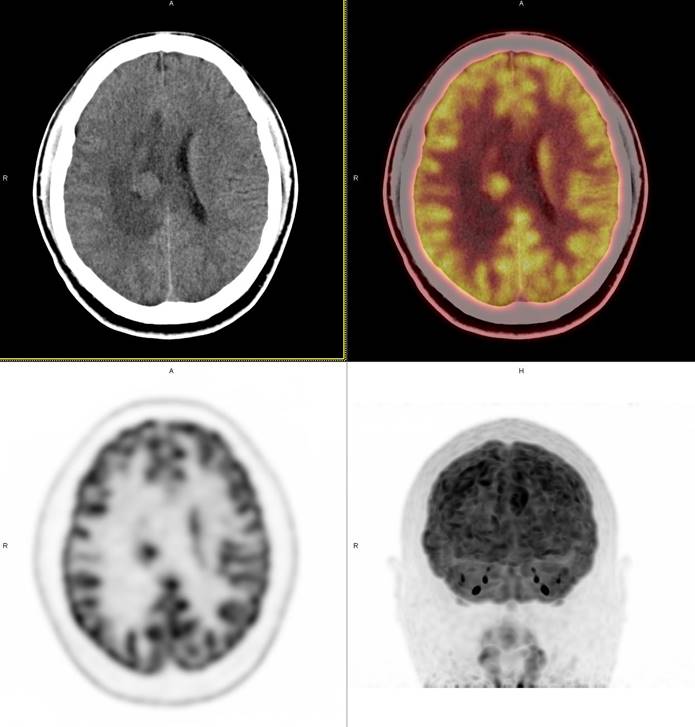

PET/CT影像圖

圖1

圖2

圖3

圖4

PET/CT檢查

影像診斷: 右側(cè)側(cè)腦室旁腦實(shí)質(zhì)內(nèi)結(jié)節(jié),代謝異常增高(SUVmax 12.13),伴瘤周水腫。

病理診斷:腦膜瘤二級(jí)

此例,PET/CT全身檢查不僅排除了轉(zhuǎn)移瘤的可能性,增高的SUV值無(wú)創(chuàng)地鑒別腦膜瘤的良惡性,充分體檢PET/CT大視野、形態(tài)與功能影像結(jié)合的優(yōu)勢(shì)。